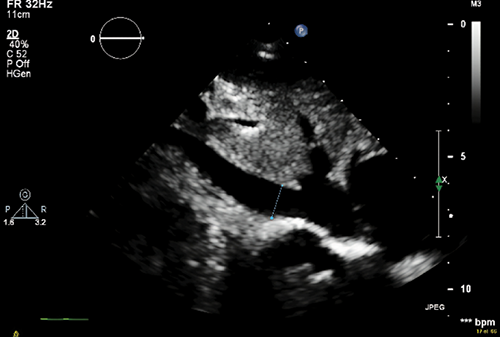

Comparison of Outcomes between Upper Arm Loop and Straight Arteriovenous Grafts in Hemodialysis Patients

Nutvara Deeratanasrikul, MD¹, Saritphat Orrapin, MD¹, Thoetphum Benyakorn, MD¹, Boonying Siribumrungwong, MD, PhD¹

388